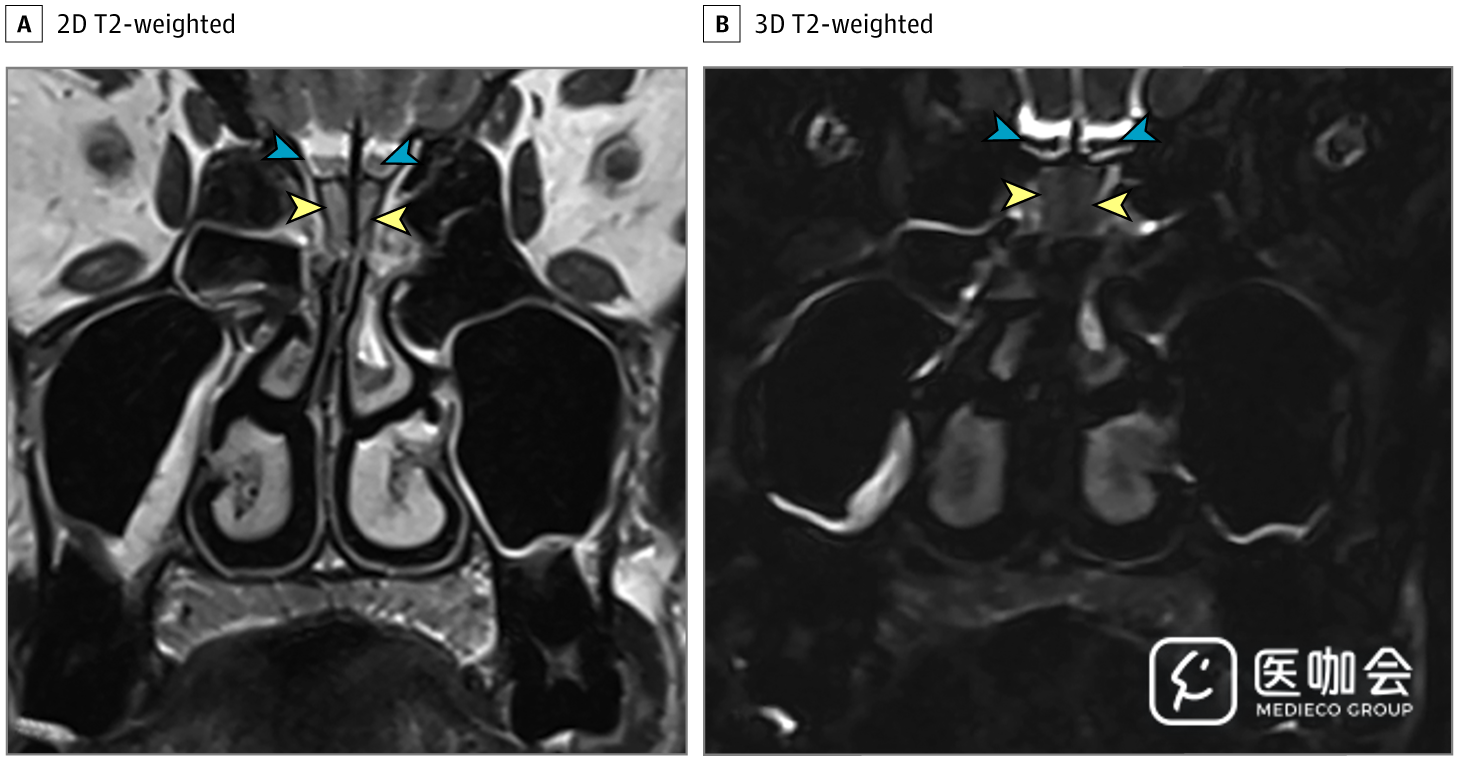

患者接受了鼻腔CT检查(图1),显示双侧嗅裂区的炎性阻塞,经鼻腔MRI再次确认了这一结果(图2)。患者的嗅球和嗅神经束未见异常。由于她的丈夫被怀疑感染了SARS-CoV-2,因此该患者也接受了SARS-CoV-2的RT-PCR,结果呈阳性。

图1